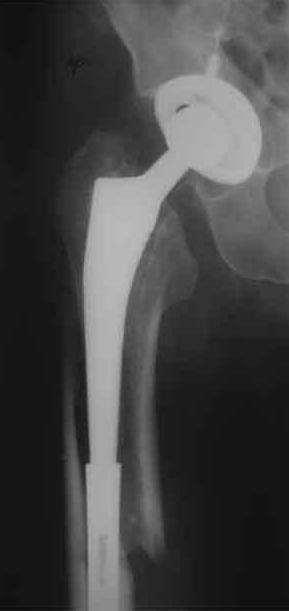

Пациента удалось осмотреть недавно. Достигнутый результат сохраняется. Перелом бедра сросся. Конечность опорная и безболезненная, ходит без трости. Ножка, похоже, реинтегрировалась, как и надеялись. Снимки и фото в приложении. Комментарии приветствуются.

Надо ли что-то делать дальше, как полагаете? Убрать винты? Убрать "удлинитель ножки"? Или оставить все, как есть? Спасибо заранее.